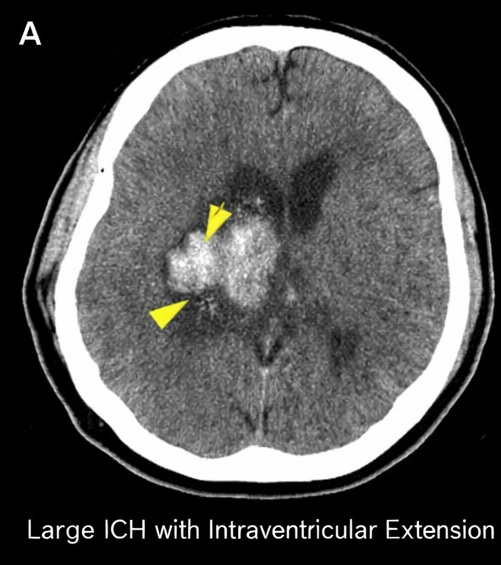

Urgent non-contrast computed tomography (CT) of the brain demonstrated a large left basal ganglia hemorrhage measuring approximately 6.2 × 4.8 × 4.5 cm with surrounding edema, intraventricular extension into the lateral ventricle, and a 7 mm midline shift.

There was effacement of the ipsilateral lateral ventricle and early signs of raised intracranial pressure. CT angiography did not reveal any underlying vascular malformation or aneurysm.

Based on clinical presentation and neuroimaging findings, a diagnosis of large acute spontaneous intracerebral hemorrhage involving the left basal ganglia with intraventricular extension and mass effect was established, most likely secondary to chronic uncontrolled hypertension.